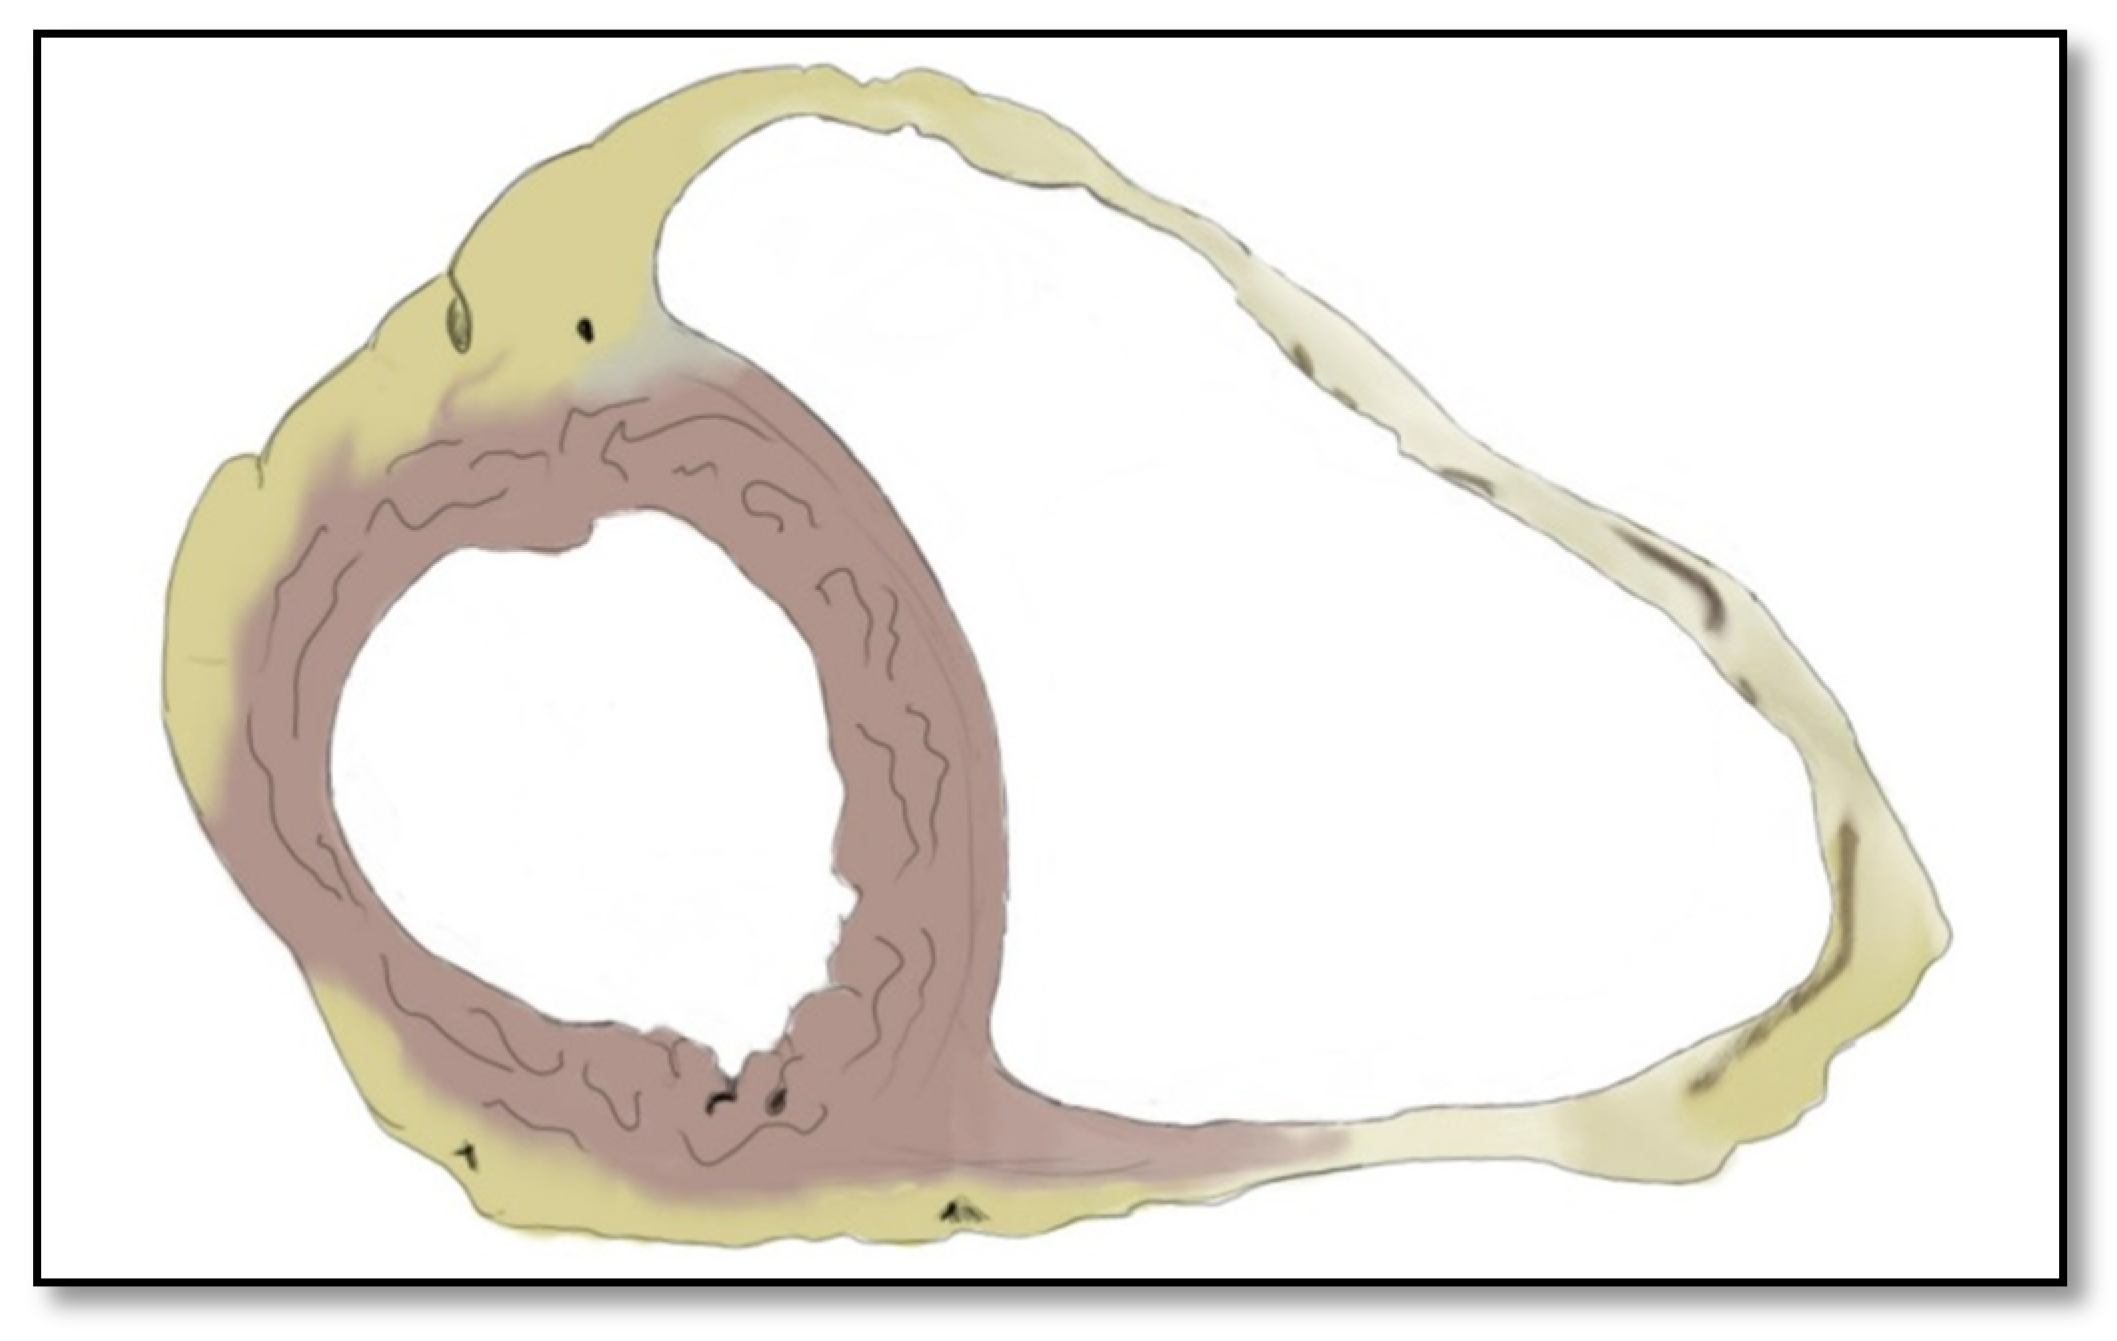

2.1. Right Ventricle Pathological Features in ARVC

2.2. Left Ventricle Pathological Features in ARVC

- Intramyocardial adipose tissue disposition—”obsolete”Although intramyocardial fat has long been a diagnostic criterion for ARVC, it is no longer used because other pathological or physiological conditions can lead to this appearance in cardiac MRI. In normal people, epicardial fat can penetrate to the myocardium and endocardium, with no clear demarcation between the epicardium and the myocardium, leading to misinterpreted images as ARVC. When intramyocardial fat is detected, it will be considered pathological only if it is associated with contraction abnormalities of the corresponding wall [12,45].Fat in ARVC appears as hyperintense intramyocardial signal at T1 spin-echo. Adipose tissue infiltrates mainly the RVOT, the free wall of the right ventricle, the intracavitary trabeculae, the moderating band, and the right side of the interventricular septum (Figure 4).Tansey et al. showed on autopsies of individuals without known heart disease that 85% of them had myocardial infiltrates with adipose tissue [46]. Mainly, the RVOT, free wall of RV wall, apex, and RV antero-lateral wall are affected, but these intramyocardial deposits do not change the thickness of the ventricular wall or the regional contraction. If the deposits extend from the epicardium to the endocardium, crossing the myocardium, then the ventricular wall may increase in size as a normal feature of the adipose distribution. It seems that these fat deposits in healthy people increase with age and are more common in obese people without being pathological [47].